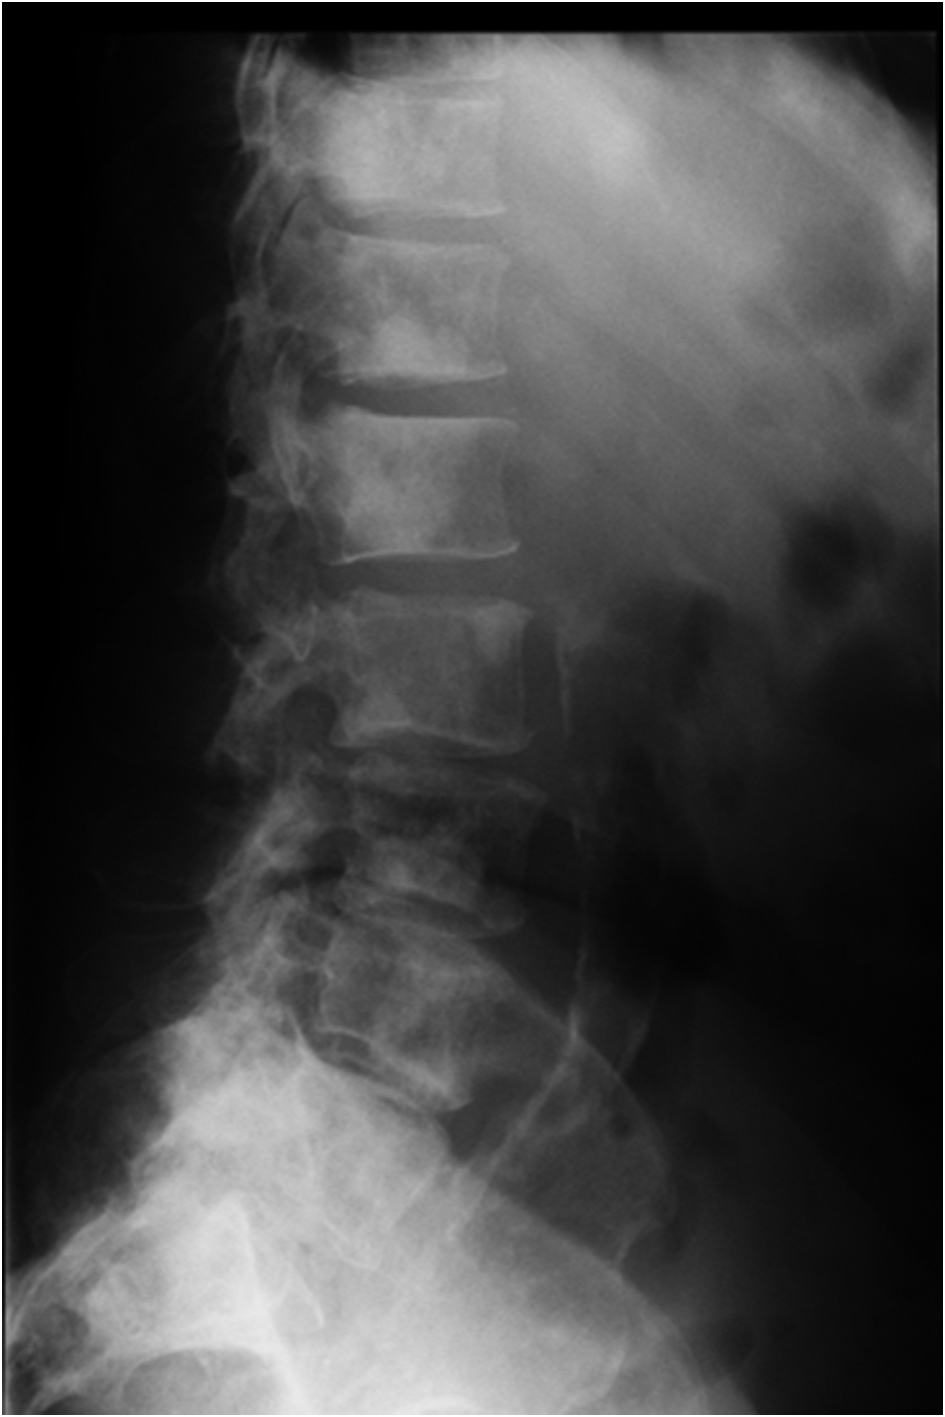

Serum electrophoresis revealed M spike with elevated IgG monoclonal protein with kappa light specificity. Urine also showed bence-jonce proteinuria with free kappa light chain. Beta 2 microglobulin levels were 32.5 mg/L. Cosyntropin stimulation test revealed primary adrenal insufficiency. Patient was started on IV hydration, dexamethasone and fludrocortisone. Patient’s electrolyte normalized on treatment and renal failure improved. Bone survey revealed lytic and blastic lesions in the vertebrae and other bones (Fig. 3). CT scan of chest also revealed large left 9th rib lesion with extra pleural mass effect. CT chest reconstruction revealed same blastic lesions in thoracolumbar vertebrae (Fig. 4). PSA, CEA and CA 19 - 9 levels were within normal limits and pelvic sonogram did not reveal any prostate nodule. HIV testing was negative and hepatitis testing revealed past infection with hepatitis B. Lymph node biopsy revealed reactive follicular hyperplasia with dermatopathic changes (Fig. 5). No other focus of malignancy was noted on CT chest, abdomen, pelvis and head. Before bone biopsy, patient’s condition deteriorated rapidly and developed DIC, GI bleed and retroperitoneal hematoma which lead to demise of the patient. Based on available data diagnosis of multiple myeloma with IgG kappa chain specificity was made.

![]() Click for large image | Figure 3. X ray of the thoraco-lumbar vertebrae showing osteoblastic lesions. |